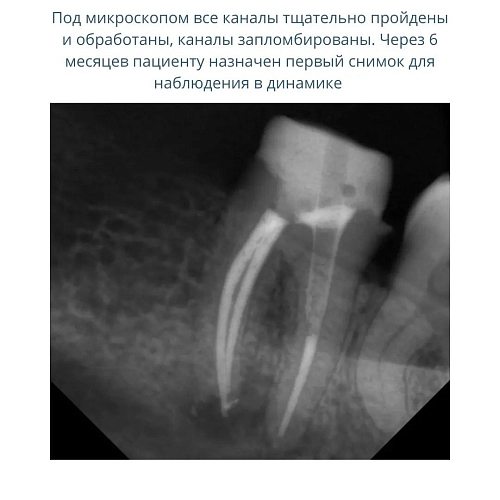

Под микроскопом проведено извлечение старого материала, прохождение всех корневых каналов и пломбирование корневых корней.

Через шесть месяцев пациенту назначен первый снимок для наблюдения в динамике.